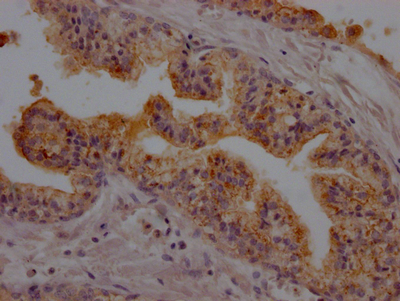

IHC image of CSB-RA927191A0HU diluted at 1:100 and staining in paraffin-embedded human prostate cancer performed on a Leica BondTM system. After dewaxing and hydration, antigen retrieval was mediated by high pressure in a citrate buffer (pH 6.0). Section was blocked with 10% normal goat serum 30min at RT. Then primary antibody (1% BSA) was incubated at 4℃ overnight. The primary is detected by a Goat anti-rabbit IgG polymer labeled by HRP and visualized using 0.05% DAB.